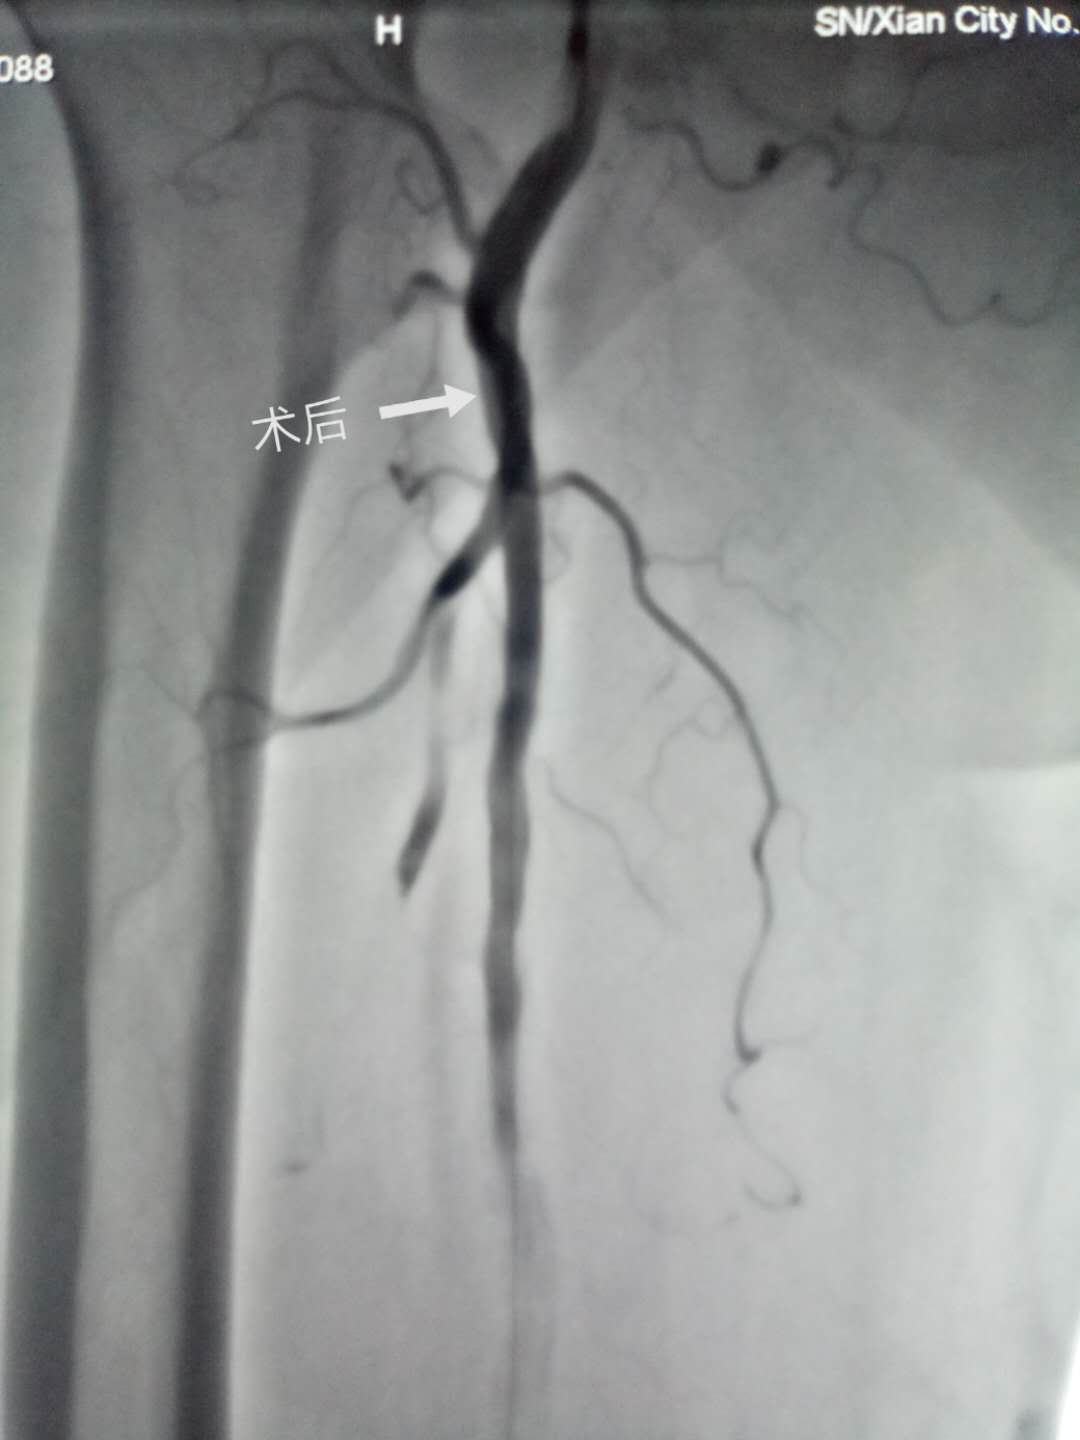

患者女性,90岁,以“间断胸闷、气短20年余,右下肢冰冷1天”之主诉入院,查体:右下肢皮肤苍白,皮温低,足背动脉搏动消失。彩超提示右下肢股动脉血栓形成,且造成管腔闭塞可能。患者为超高龄女性,体重只有38公斤,同时合并2型糖尿病、冠心病、心力衰竭等疾病,属于出血超高危险患者。现急性右下肢动脉血栓形成,需要急诊介入治疗,否则有肢体坏死的风险。在郭瑄主任医师主持下,经全科积极讨论确定右下肢动脉血栓形成的微创治疗方案。认真完成术前准备后,充分告知家属手术风险,由郭瑄主任医师、尚粉青副主任医师在介入室配合下于2019年4月10日下午在局麻下行右下肢动脉血管造影术+血栓抽吸术+动脉血栓溶栓术,手术过程顺利,术后患者右下肢供血明显改善。